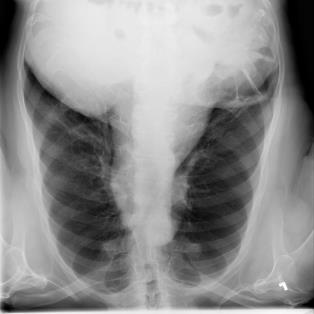

The COVID-19 disease was first discovered in Wuhan, China, and spread quickly worldwide. After the COVID-19 pandemic, many researchers have begun to identify a way to diagnose the COVID-19 using chest X-ray images. The early diagnosis of this disease can significantly impact the treatment process. In this article, we propose a new technique that is faster and more accurate than the other methods reported in the literature. The proposed method uses a combination of DenseNet169 and MobileNet Deep Neural Networks to extract the features of the patient's X-ray images. Using the univariate feature selection algorithm, we refined the features for the most important ones. Then we applied the selected features as input to the LightGBM (Light Gradient Boosting Machine) algorithm for classification. To assess the effectiveness of the proposed method, the ChestX-ray8 dataset, which includes 1125 X-ray images of the patient's chest, was used. The proposed method achieved 98.54% and 91.11% accuracies in the two-class (COVID-19, Healthy) and multi-class (COVID-19, Healthy, Pneumonia) classification problems, respectively. It is worth mentioning that we have used Gradient-weighted Class Activation Mapping (Grad-CAM) for further analysis.